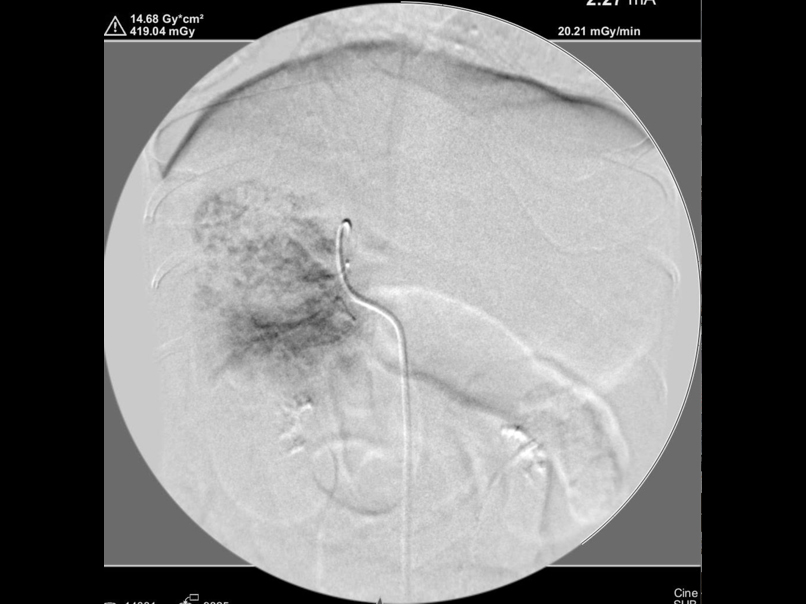

造影での腫瘍の評価

腫瘍塞栓後の造影検査